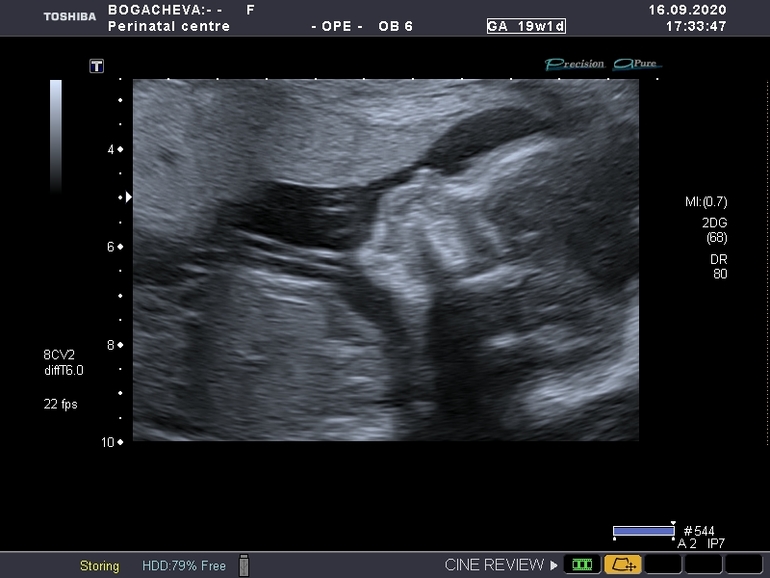

2ой скрининг

Сегодня было видео свидание с моим пупсом. Ну он правда выглядит как пупс. Крутился весь но врач все равно все посчитал и померил. Были группа студентов врачей. И поэтому очень подробно все рассказывали)) сын начал жевать не пойми что, потом стал икать. В конце еще зевал. Жизнь там у него какая то. Мне кажется что это самый красивый ребеночек